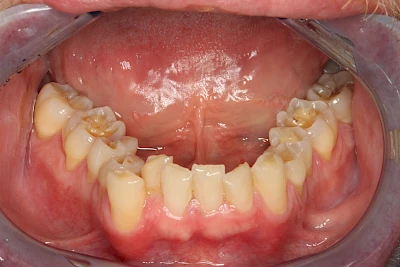

- Abnutzung durch Kauen (Abrasion) oder duch durch übermäßiges Knirschen bzw. Pressen (Attrition)

- Knirschen bzw. Pressen und ungünstige Putztechnik (Druck): keilförmige Defekte